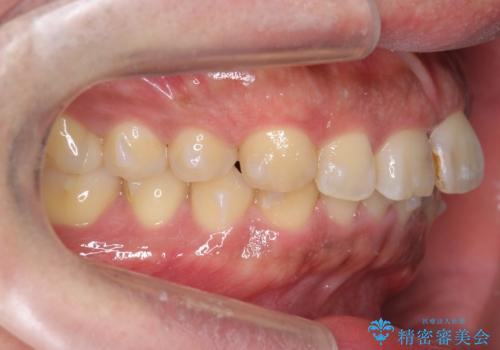

前歯のねじれを 1年かけずに矯正 インビザライン

- 前歯のねじれを主訴に来院。

インビザラインで治療しました。